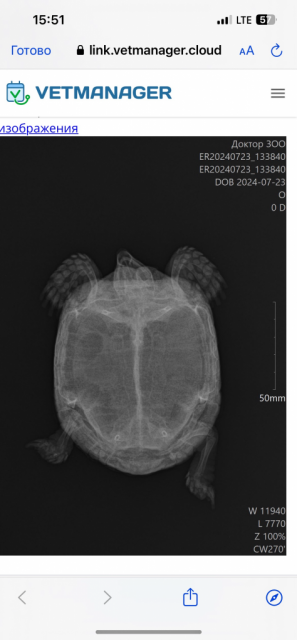

8-9.  Возраст - около 18 лет. Вес ≈ 300 г. Размеры - 15 см. от головы до хвоста. Заболела основательно две с половиной недели назад. Хотя изначально всё начиналось с рвоты питомца от банана и ягод, где содержалось много сока. Три  недели назад приступы рвоты увеличились до 2-3 раз в день. Есть отказалась совсем примерно в это же время. Ни моча, ни кал не выходили. Рвота оставалась, но ничего не выходило. Повезли в ветеринарную клинику  «Доктор Зоо», врач - Кадкин Алексей Петрович. Сделали рентген (1 фото), сказали, что по нему всё отлично. Предположили, что это гастрит и назначили антибиотики— проз Энромаг по 0.1 мл п/к 1 раз в день. Кололи 5 дней. Также давали витамины — крас Бутофан по 1 кап 1 раз в день 7 дней. 30 июля заметили, что черепаха начала дышать ртом, практически не просыпалась и не реагировала ни на что. Врач сказал, что она «собирается умирать» (цитата) и назначит подкормку глюкозой 5% по 2 мл 3 раза в день 5 дней. А также витамины — тетрамаг по 1 кап 1 раз в день 7 дней. Глюкозу вводили, ей становилось лучше. Стала дышать носом, просыпаться, активничать. Сходила в туалет странно (2 фото). Также стали кормить её через шприц, так как аппетита не было и нет. Спустя 4 дня привезли её ещё раз на осмотр, так как дыхание ртом продолжалось, но не часто. Врач сказал, что у неё отёк лёгких из-за недостаточного питания. Про туалет сказал, что это нормально, так как был курс антибиотиков и кишечник стал работать. Что это нормально, и она восстановится потихоньку. Однако вчера и сегодня черепаха стала дышать исключительно ртом, издавая свистящие звуки. Дышит тяжело, очень глубоко, но редко. Также на протяжении всей болезни присутствует «надутость» (3 фото). Сегодня обзвонили все ветеринарные клиники, все врачи, которые занимаются черепашками, на выходных. А тот самый врач, который лечил питомца, отказался её смотреть.